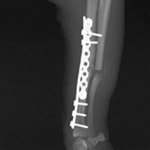

脛骨骨折 : 症例1 | 症例2 | 症例3 | 症例4 | 症例5

Advanced Locking plate system と Locking compression plate system

当院ではAdvanced Locking plate system(ALPS)と、Locking compression plate system(LCPS)という骨接合法で骨折症例の治療を行っています。

Locking Compression Plate

LCPは、スクリュー(ネジ)とプレート(金属の板)をロックする特殊な構造により骨折部位を固定する新しい世代のプレートシステムです。ひとつのホールでロッキングスクリューとスタンダードスクリューの使用を選択できるユニークな構造をしているため、骨折断端間の圧迫を目的とした従来型プレート固定法に加え、高い角度安定性を有するロッキングスクリューを用いた固定法の選択が可能です。従来のプレートシステムでは困難だった部分の骨折や癒合不全の症例に高い治療効果をもたらします。